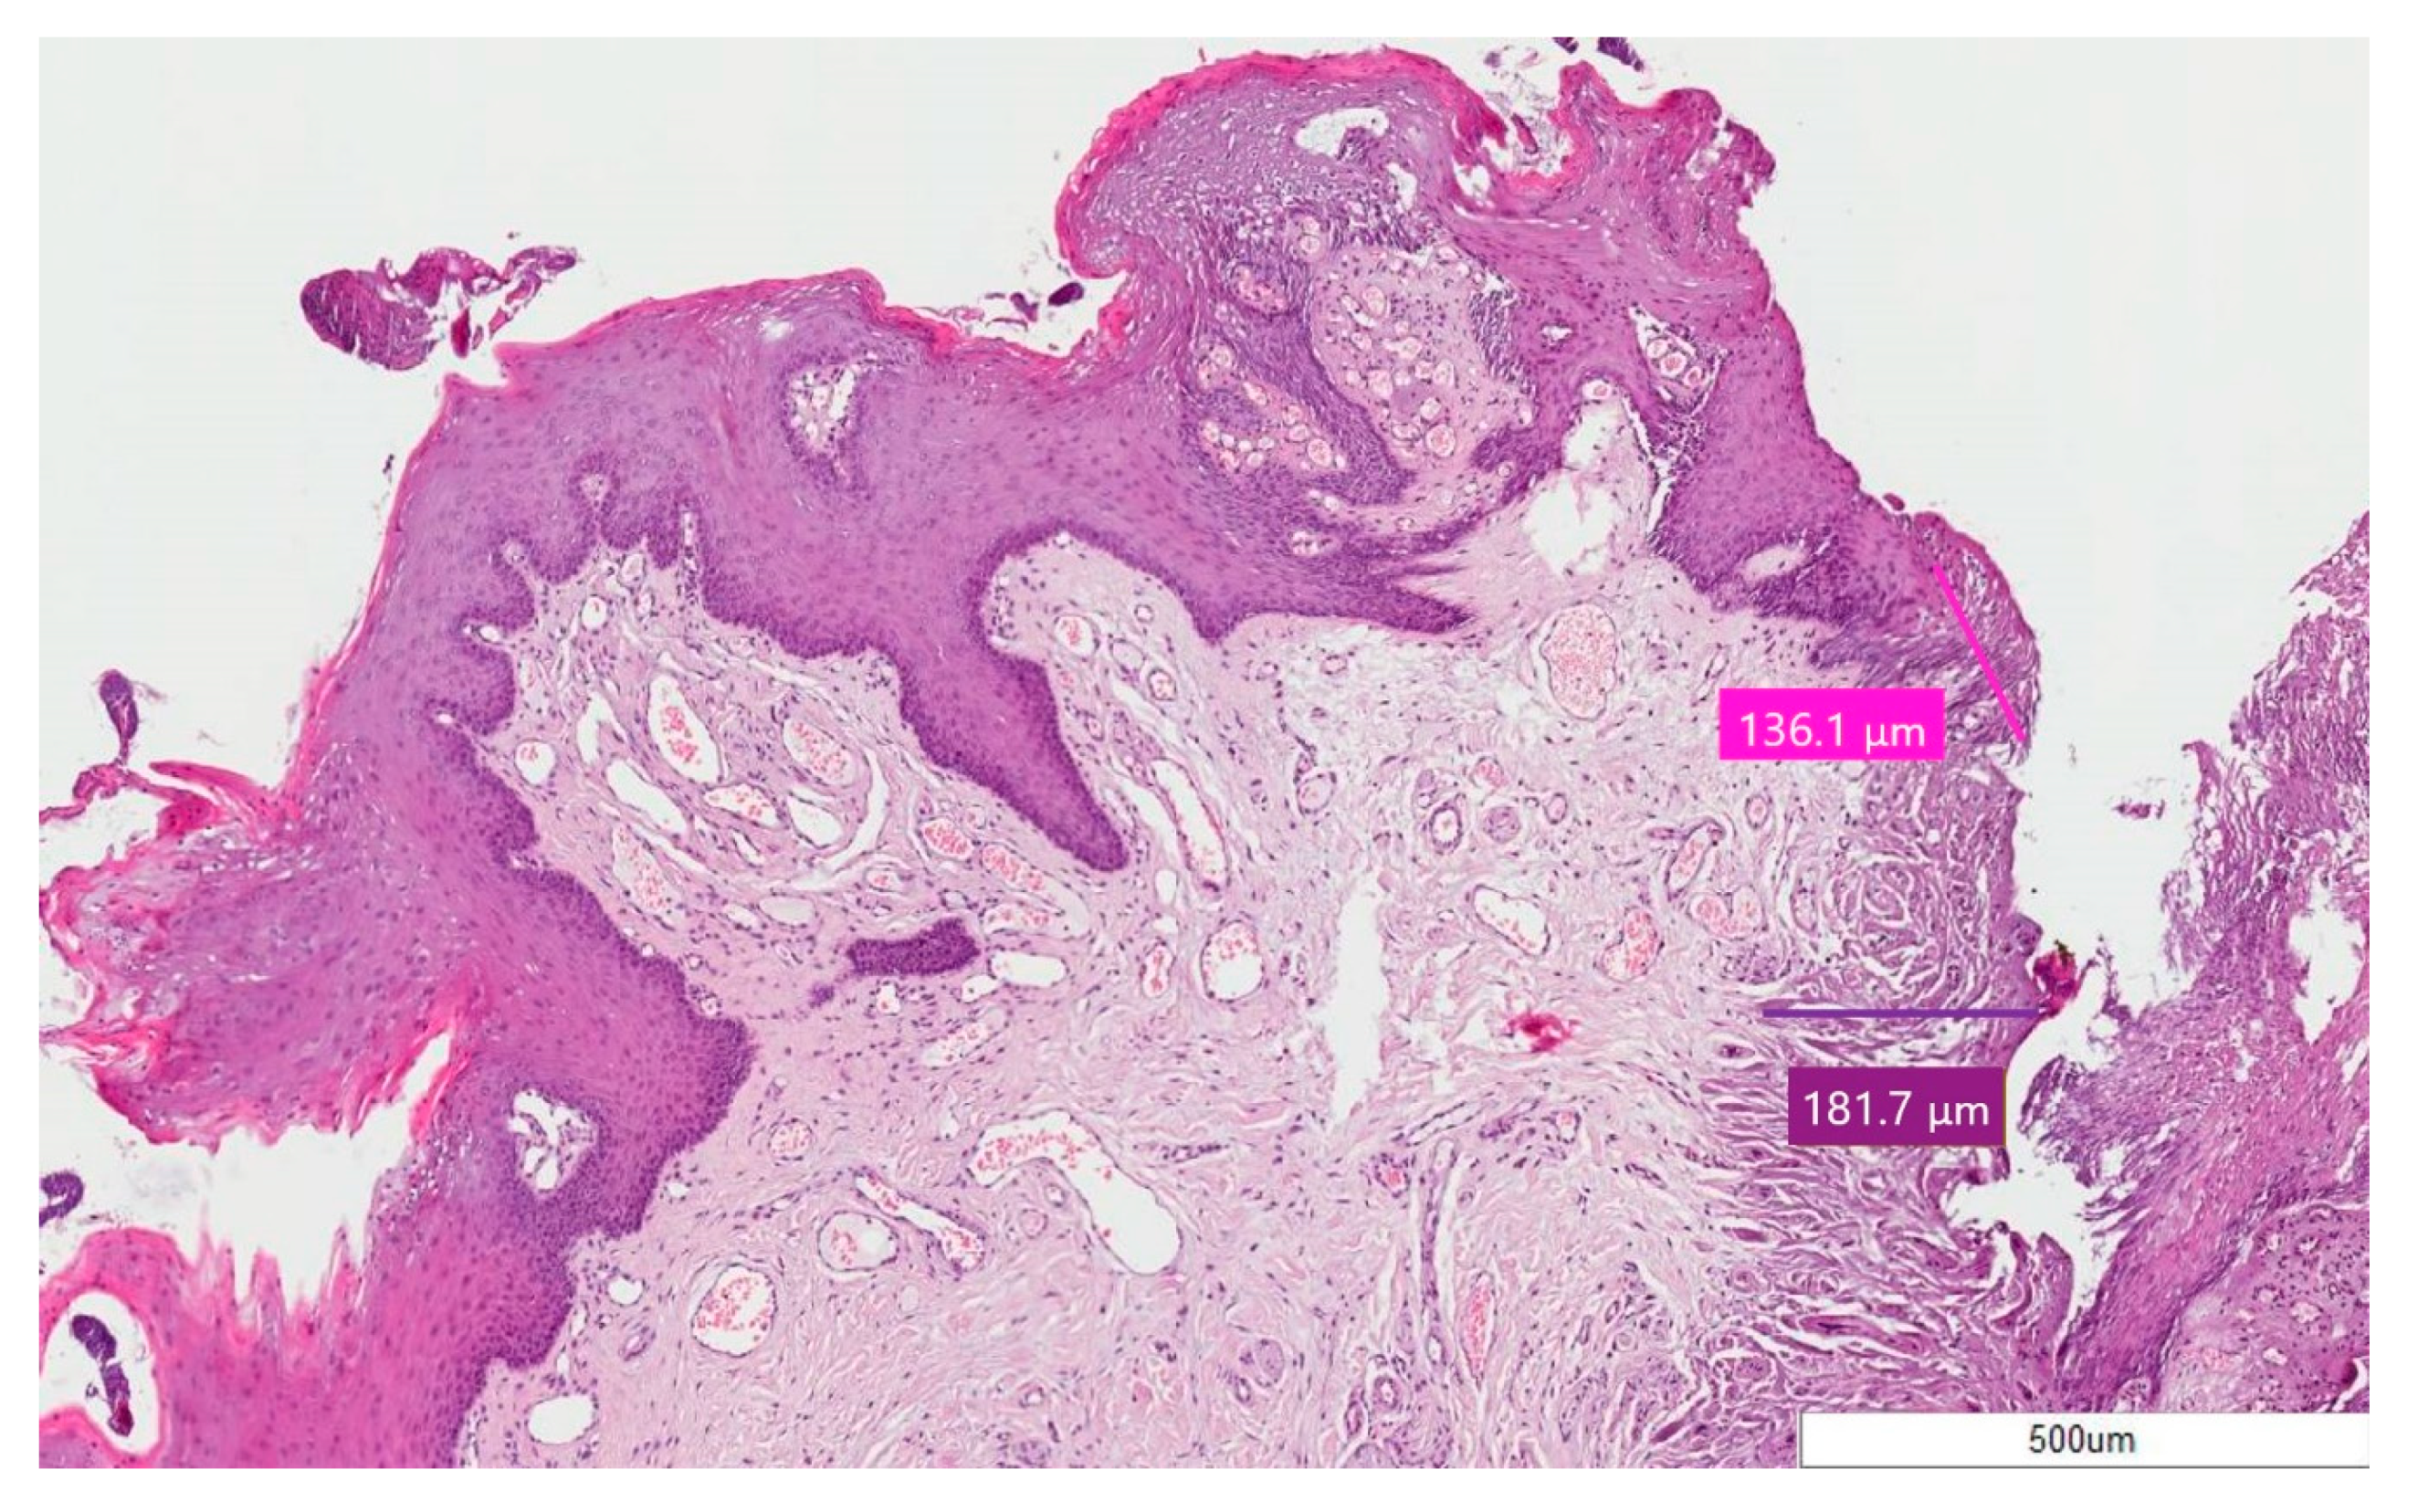

| 2. | Squamous Papilloma | 136.1 ± 311.96 | 181.7 ± 264.23 | 317.8 ± 505.37 |